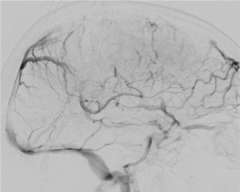

Figure 3

Anticoagulation, the administration of a blood thinning drug is the first line of treatment and has been shown to be very effective. However, when the clot burden is too large and/or the patient condition deteriorates despite anticoagulation treatment, catheter based clot-busting treatment becomes a consideration (Figure 3).

Using the state-of-the-art interventional suite equipped with the latest biplane X-ray machine, we can safely navigate a catheter into the cerebral venous sinus that is blocked with the clot. Via the catheter, we can deploy a clot-capturing device or aspirate the clot from the catheter itself.